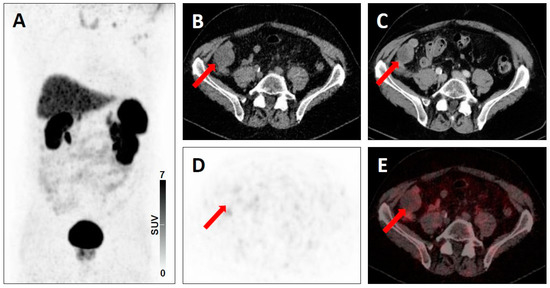

| 3 | 3A | - Regional lymph nodes, e.g. low-level uptake in mesenteric lymph node in midabdomen [20] - Mild radiotracer uptake in a supraclavicular lymph node [5] | - Pelvic lymph node involvement with low-level uptake [19] |

| 3B | - Low-level uptake in a rib with lack of anatomic correlate [20] | - Low level-uptake in the iliac bone with lack of anatomic correlate [19] | |